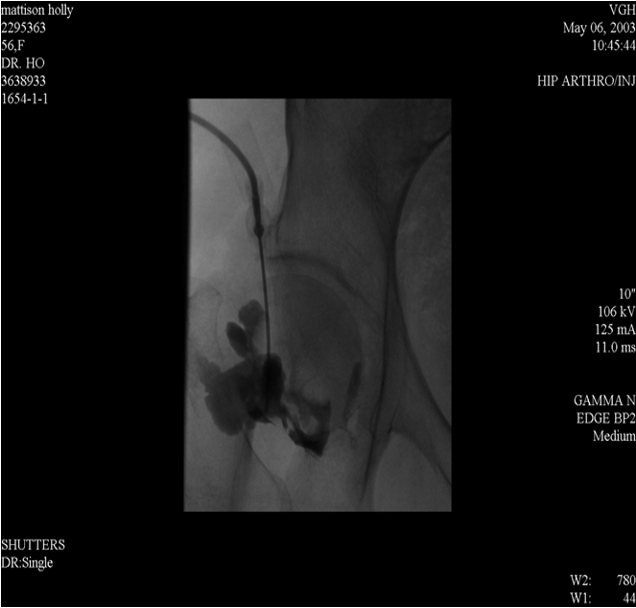

Arthrography

Arthrography is introduction of contrast agent e.g. positive contrast such as iodine solution and negative contrast such as air or combination of both into the joint space.